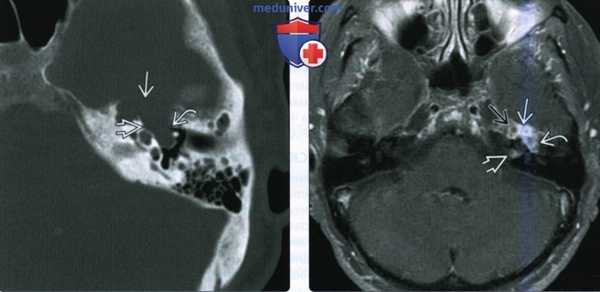

(Слева) При аксиальной КТ в костной окне определяется объемное образование в расширенной ямке коленчатого ганглия с распространением опухоли вдоль переднего барабанного сегмента ЧН VII со смещением слуховых косточек латерально. Наружная поверхность слуховой капсулы истончена ШЛН.

(Справа) При аксиальной МРТ Т1 С+ FS у этого же пациента визуализируется контрастирующаяся ШЛН, расположенная в коленчатом ганглии. Опухоль распространяется вдоль барабанного сегмента ЧН VII и во внутренний слуховой канал по лабиринтному сегменту ЧН VII. Обратите внимание на интрамуральную кисту медиально.

(Слева) При аксиальной КТ в костном окне у пациента с полипом в наружном слуховом канале определяется опухоль неправильной формы, расположенная в области сосцевидного сегмента ЧН VII.

(Справа) При аксиальной MPT Т1 ВИ С+ FS у этого же пациента определяется контрастирующаяся ШЛН в сосцевидном сегменте ЧН VII, выбухающая через костный дефект в НСК.

(Слева) При корональной МРТ Т1 ВИ С+ FS у пациента с кондуктивной тугоухостью и подергиванием мышц лица определяется мультифокальная контрастирующаяся ШЛН, проникающая в ячейки сосцевидного отростка и книзу вдоль сосцевидного сегмента ЧH VII.

(Справа) При аксиальной МРТ Т1 С+ визуализируется контрастирующееся образование, выбухающее в медиальные отделы средней черепной ямки из большого поверхноаного каменистого нерва. Диагноз ШЛН можно заподозрить при распространении по ходу барабанного и лабиринтного ЧН VII во внутренний слуховой канал.